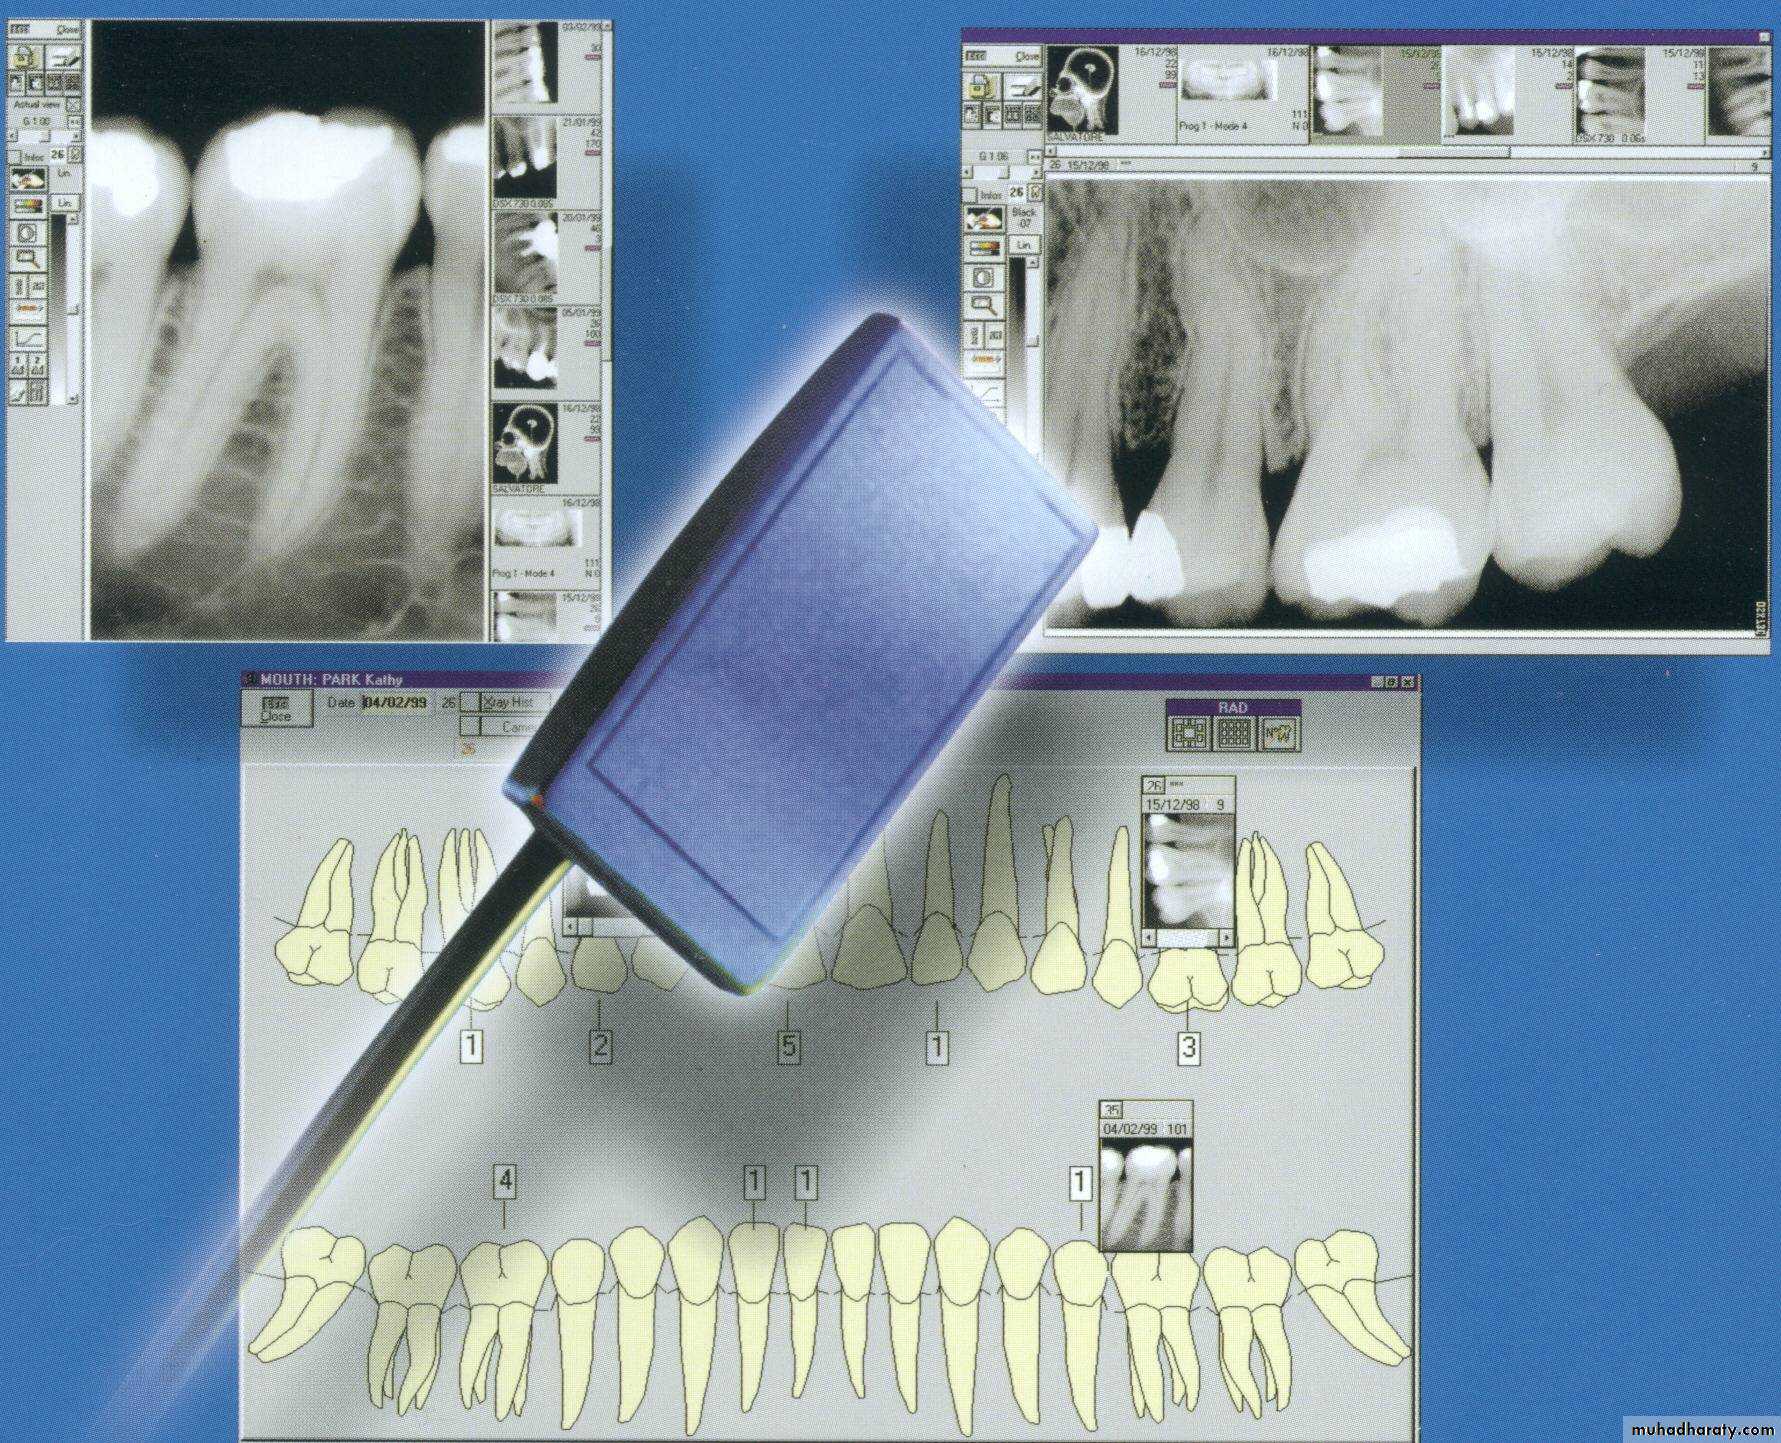

Advanced Radio.-Digital radiography

-Image recorded with non film receptorThe film replaced by flat electronic pad or sensor

-Images sent to computer displayed on monitor screen